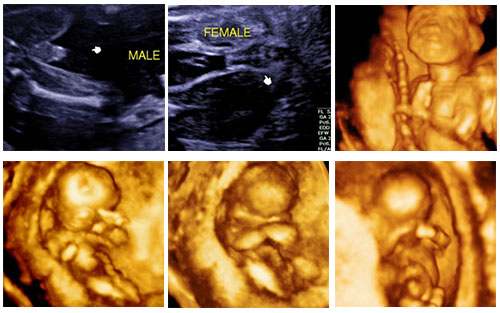

อัลตราซาวด์ … เทคโนโลยีช่วยส่องทารกในครรภ์มารดา

การตั้งครรภ์ คงเป็นความสุขของคนที่ได้ชื่อว่ากำลังจะเป็นคุณพ่อคุณแม่ป้ายแดง คุณพ่อคุณแม่จะพยายามทำทุกอย่างที่จะบำรุงให้ลูกน้อยที่อยู่ในครรภ์สมบูรณ์